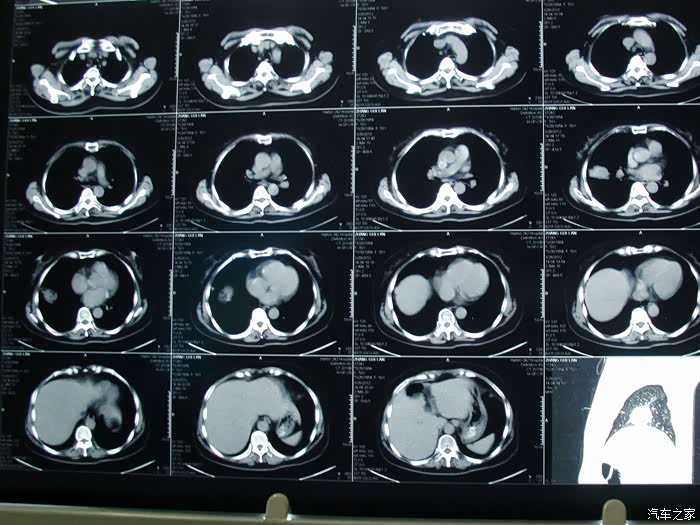

(本图片来源于网络)

胸部的影像学检查也是确定新型冠状病毒感染者或疑似病例的重要指标。早期感染患者呈现多发小斑片影及间质改变,以肺外带明显。进而发展为双肺多发磨玻璃影、浸润影,严重者可出现肺实变,胸腔积液少见。 如果这些依旧没有问题,那么我们就可以回家继续看汽车之家的帖子。